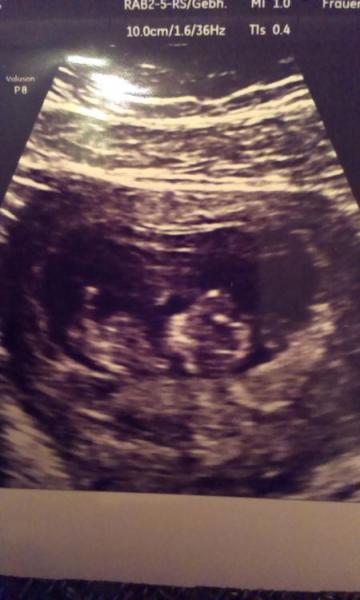

Heyyy ihr lieben Mitschwangeren Ich bin zurück von meinem Termin und super glücklich! Sry, dass ich mich erst jetzt melde, war bei meiner Ausbildung Also meinem Wurm geht es ganz prima! Es ist schon fast 4 cm groß und damit sogar etwas größer als der üblicher Weise angegebene Wert für 10+1. ET am 30.3. bleibt aber. Erst war es ganz ruhig, aber als ich dann gesagt hab, dass es sich bewegen soll hat es mich scheinbar gehört und kräftig gewunken, gestrampelt und gezappelt Bin auf jeden Fall total verliebt und Stolz, wie groß mein kleines Wunder schon ist

Hier noch ein Bildchen man ist das alles aufregend, soweit hab ichs das letzte Mal nicht geschafft